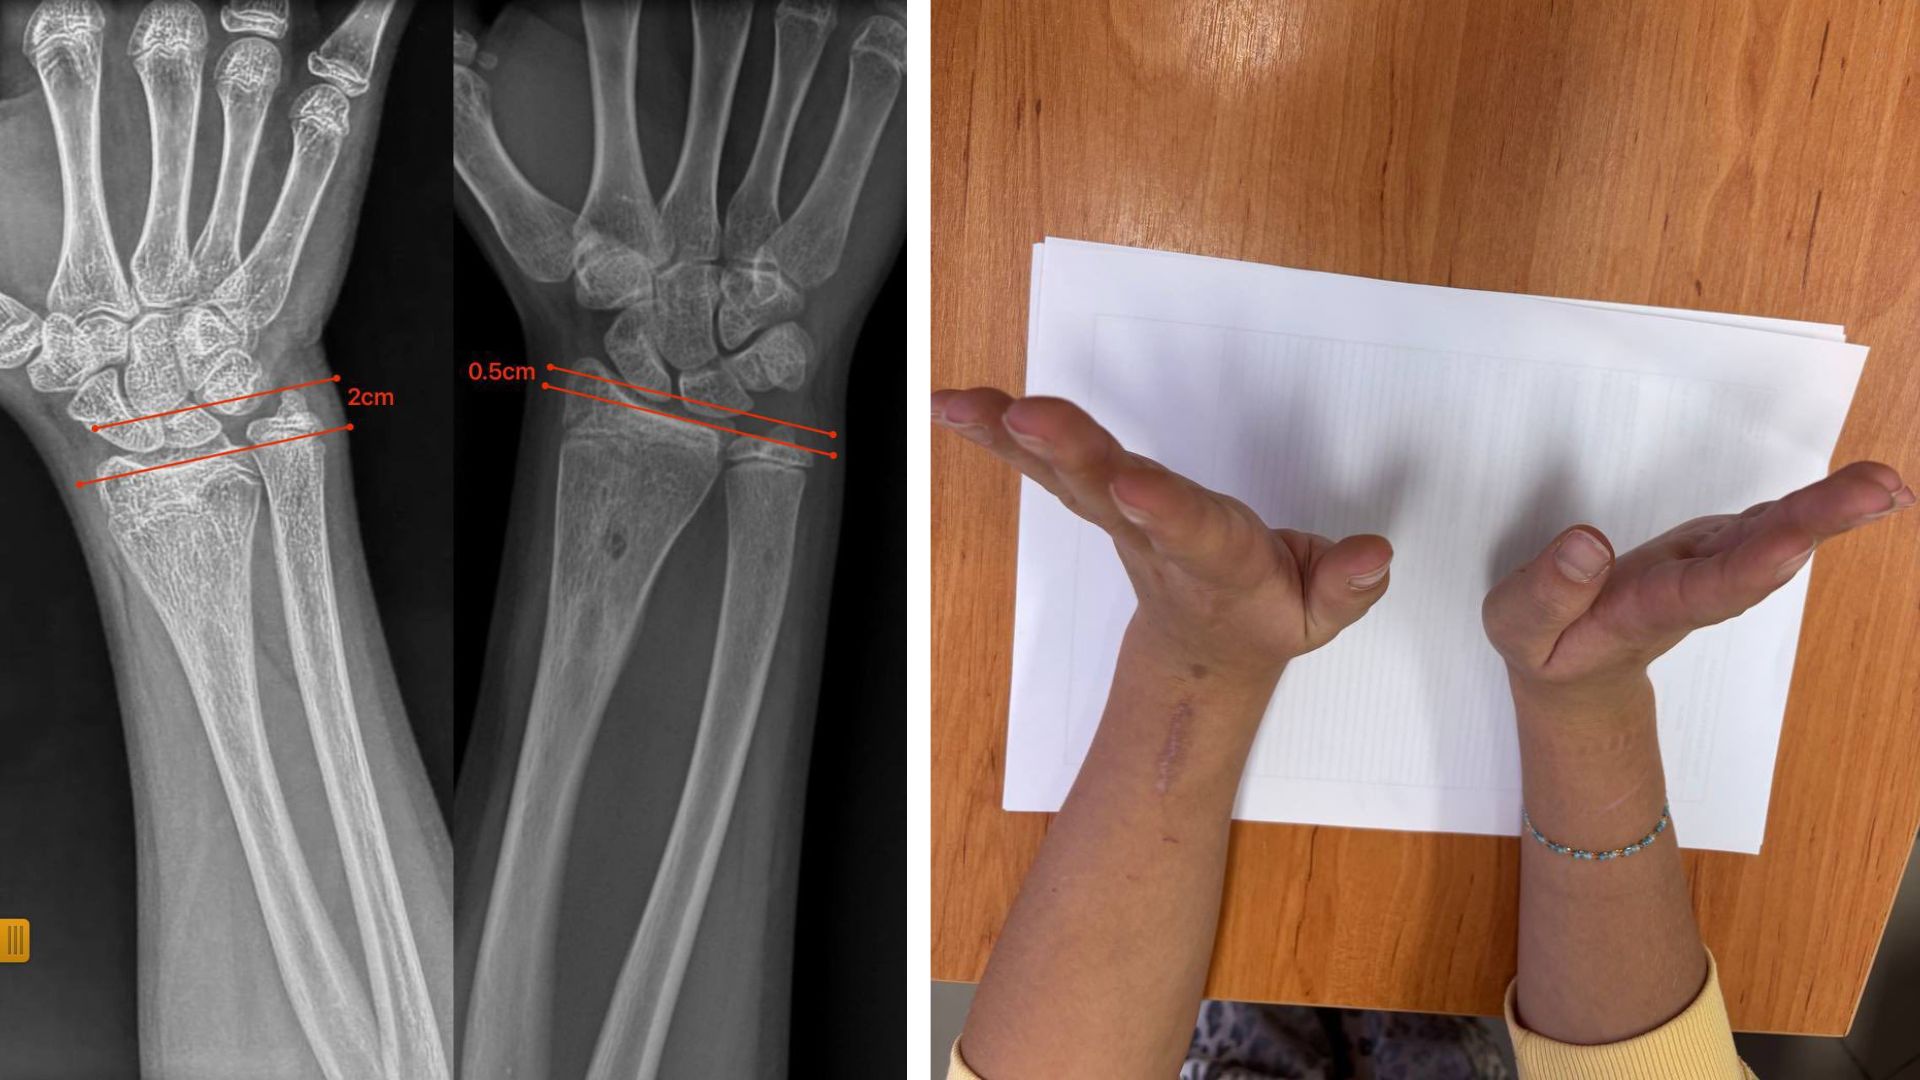

В ортопедо-травматологічному відділенні Закарпатської обласної дитячої лікарні успішно провели малотравматичну операцію 12-річній дівчинці з післятравматичною деформацією передпліччя. Через травму в неї утворився кістковий місток, який заблокував ріст кістки та спричинив її викривлення. Під час втручання лікарі ендоскопічно видалили кістковий місток, без остеотомій та встановлення металоконструкцій. Уже за сім місяців ріст кістки нормалізувався, форма передпліччя відновилася, а рухливість кінцівки збережена.